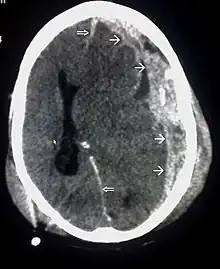

| CT scan showing cerebral contusions, hemorrhage within the hemispheres, and subdural hematoma. There is also displaced skull fracture of left transverse parietal and temporal bones.[2] | |

Systems also exist to classify TBI by its pathological features.[67] Lesions can be extra-axial, (occurring within the skull but outside of the brain) or intra-axial (occurring within the brain tissue).[93] Damage from TBI can be focal or diffuse, confined to specific areas or distributed in a more general manner, respectively.[94] However, it is common for both types of injury to exist in a given case.[94]

Hematomas, also focal lesions, are collections of blood in or around the brain that can result from hemorrhage.[24] Intracerebral hemorrhage, with bleeding in the brain tissue itself, is an intra-axial lesion. Extra-axial lesions include epidural hematoma, subdural hematoma, subarachnoid hemorrhage, and intraventricular hemorrhage.[105] Epidural hematoma involves bleeding into the area between the skull and the dura mater, the outermost of the three membranes surrounding the brain.[24] In subdural hematoma, bleeding occurs between the dura and the arachnoid mater.[32] Subarachnoid hemorrhage involves bleeding into the space between the arachnoid membrane and the pia mater.[32] Intraventricular hemorrhage occurs when there is bleeding in the ventricles.[105]